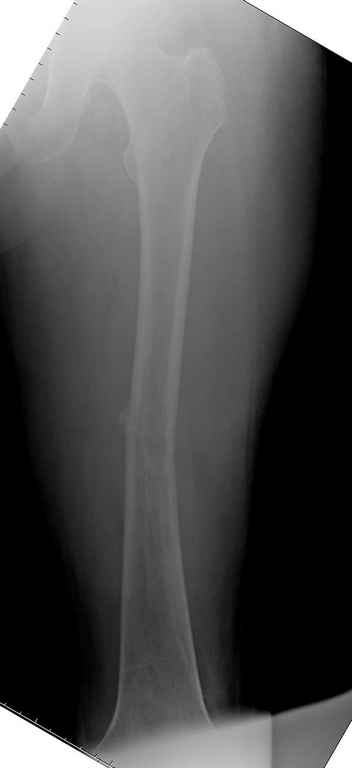

Здесь случай 66 летней пациентки со спонтанными болями в левой нижней конечности, обратилась в приемное, сделаны снимки бедра и КТ.

Патологический перелом бедра, конечность на вытяжении.

Известно, что многие из нас независимо от метода лечения и стадии первичной опухоли проводят интрамедуллярное штифтование при различных патологических состояниях бедра, включая патологические переломы.

С минимальным рассверливанием и ретроградным методом провели остеосинтез бедра 12 мм гвоздем. (17-20)

Кровопотеря во время операции меньше 100 мл.